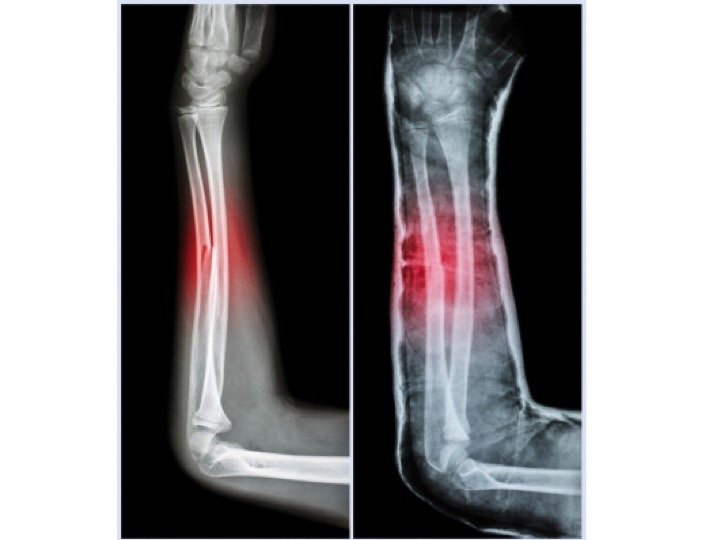

Fractured Ulna Arm Bone Photograph by Zephyr/science Photo Library

Fractured Ulna Arm Bone Photograph by Zephyr/science Photo Library Arm Bone Ulna Fracture Learn about the causes, symptoms, and treatment of broken radius and ulna bones in the middle of the forearm. What is a broken arm? One of the most common causes. A broken arm is a bone fracture (broken bone) in your arm. A forearm fracture can affect the radius or the ulna, or both bones, and may require surgery or. Arm Bone Ulna Fracture.